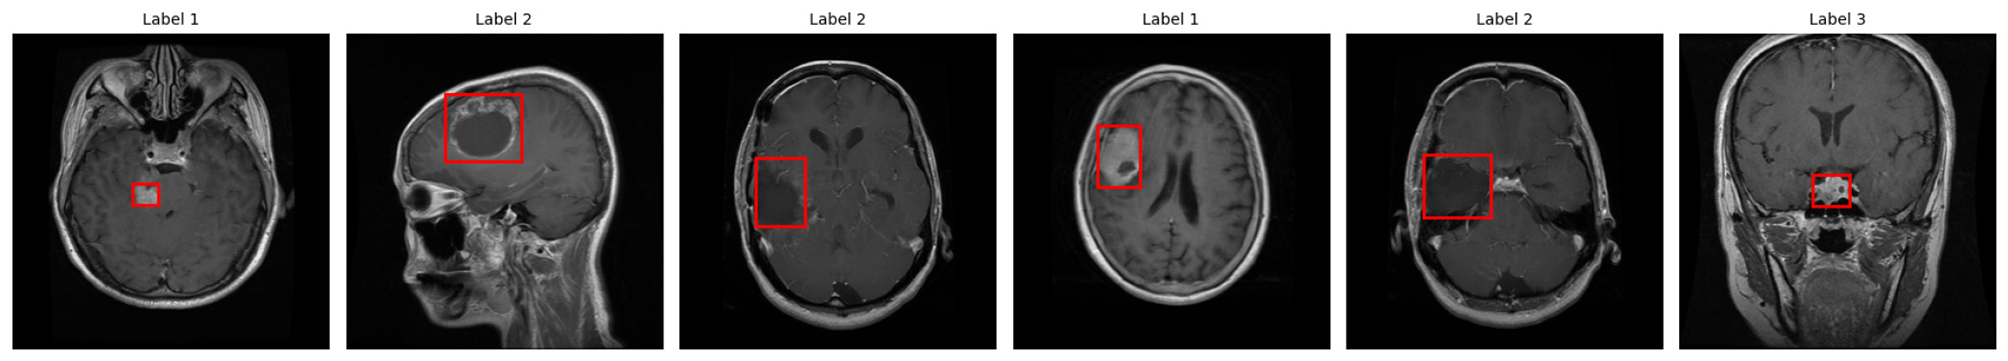

Upon completion of the verification process, the labeled MRI images are prepared for YOLOv5 training, as presented in Figure 4. Each of the red bounding boxes represents boxes of detected tumorous areas, and the numbers 1–3 refer to the classes of glioma, meningioma, and pituitary. This visual representation proves the persistent annotation agreement in the entire dataset.

Figure 4

Annotated MRI images used for YOLOv5 training, with red bounding boxes marking tumor regions and class labels (1: glioma, 2: meningioma, 3: pituitary).